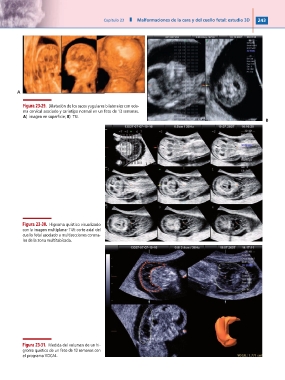

Figura 23-29. Dilatación de los sacos yugulares bilaterales con ede-

ma cervical asociado y cariotipo normal en un feto de 13 semanas.

A) imagen en superficie; B) TUI.

Figura 23-30. Higroma quístico visualizado

con la imagen multiplanar TUI: corte axial del

cuello fetal asociado a multisecciones corona-

les de la zona multitabicada.

Figura 23-31. Medida del volumen de un hi-

groma quístico de un feto de 12 semanas con

el programa VOCAL.